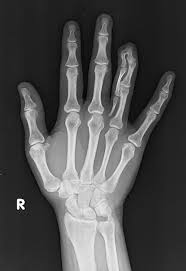

Anatomy Musculoskeletal X Ray Google Search Radiology Student Medical Anatomy Medical Knowledge